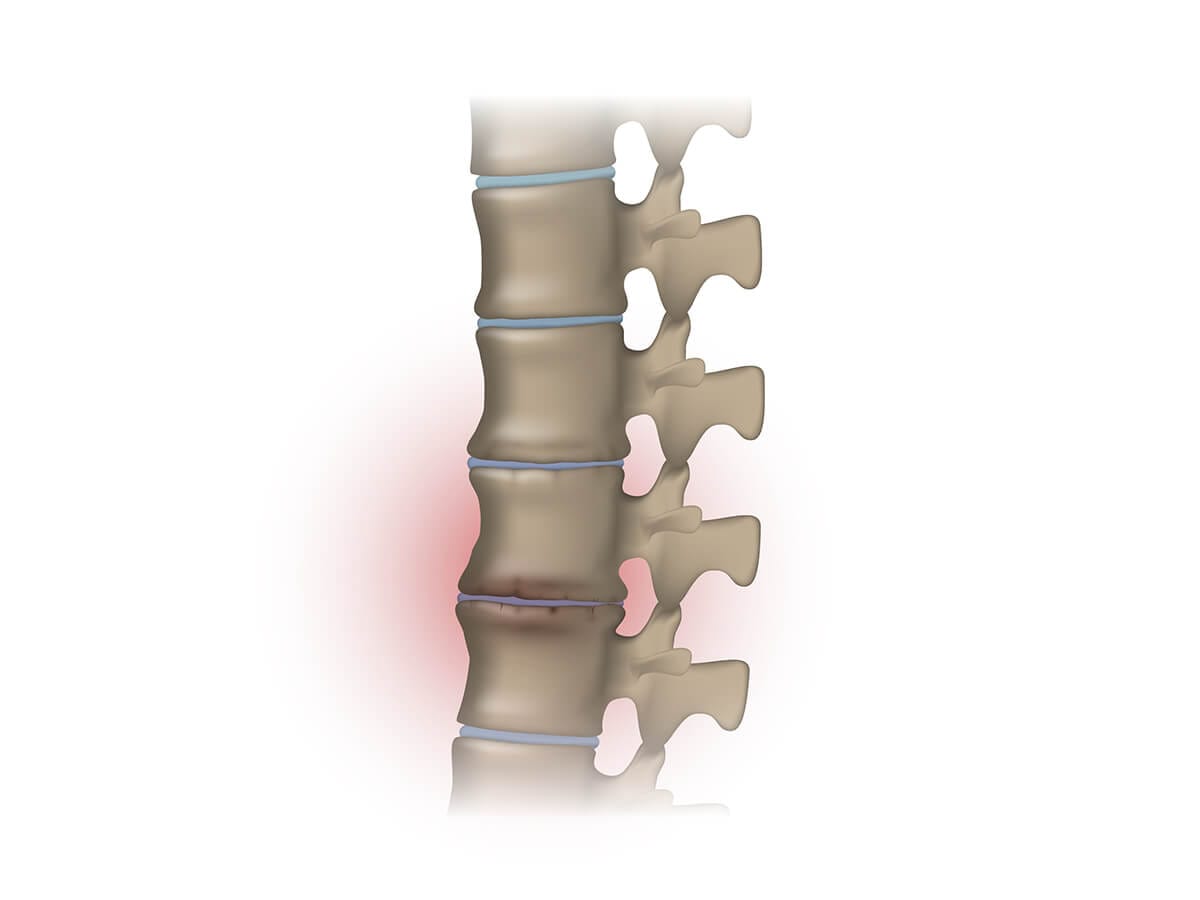

What Is Spinal Stenosis?

Spinal stenosis occurs when spaces in the spine narrow and compress the nerves. It most often affects adults over 50 and commonly presents as:

There are two main types:

1. Central Canal Stenosis

Narrowing of the main spinal canal — often from disc bulges, arthritis, or ligament thickening.

2. Foraminal Stenosis

Narrowing of the openings where nerves exit the spine — often caused by disc height loss or bone spurs (often known as Disc Degenerative Disease).Both types can respond very well to structured, non-surgical management.